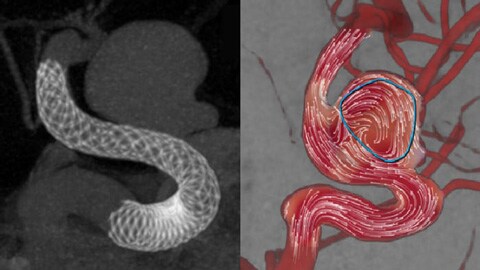

SmartCT Vaso report

SmartCT Vaso

SmartCT Vaso enables visualization of both low contrast soft tissue, contrast enhanced vessels and high contrast objects such as flow diverters, stents, intrasaccular devices and coils in one view which allows users to assess device deployment.